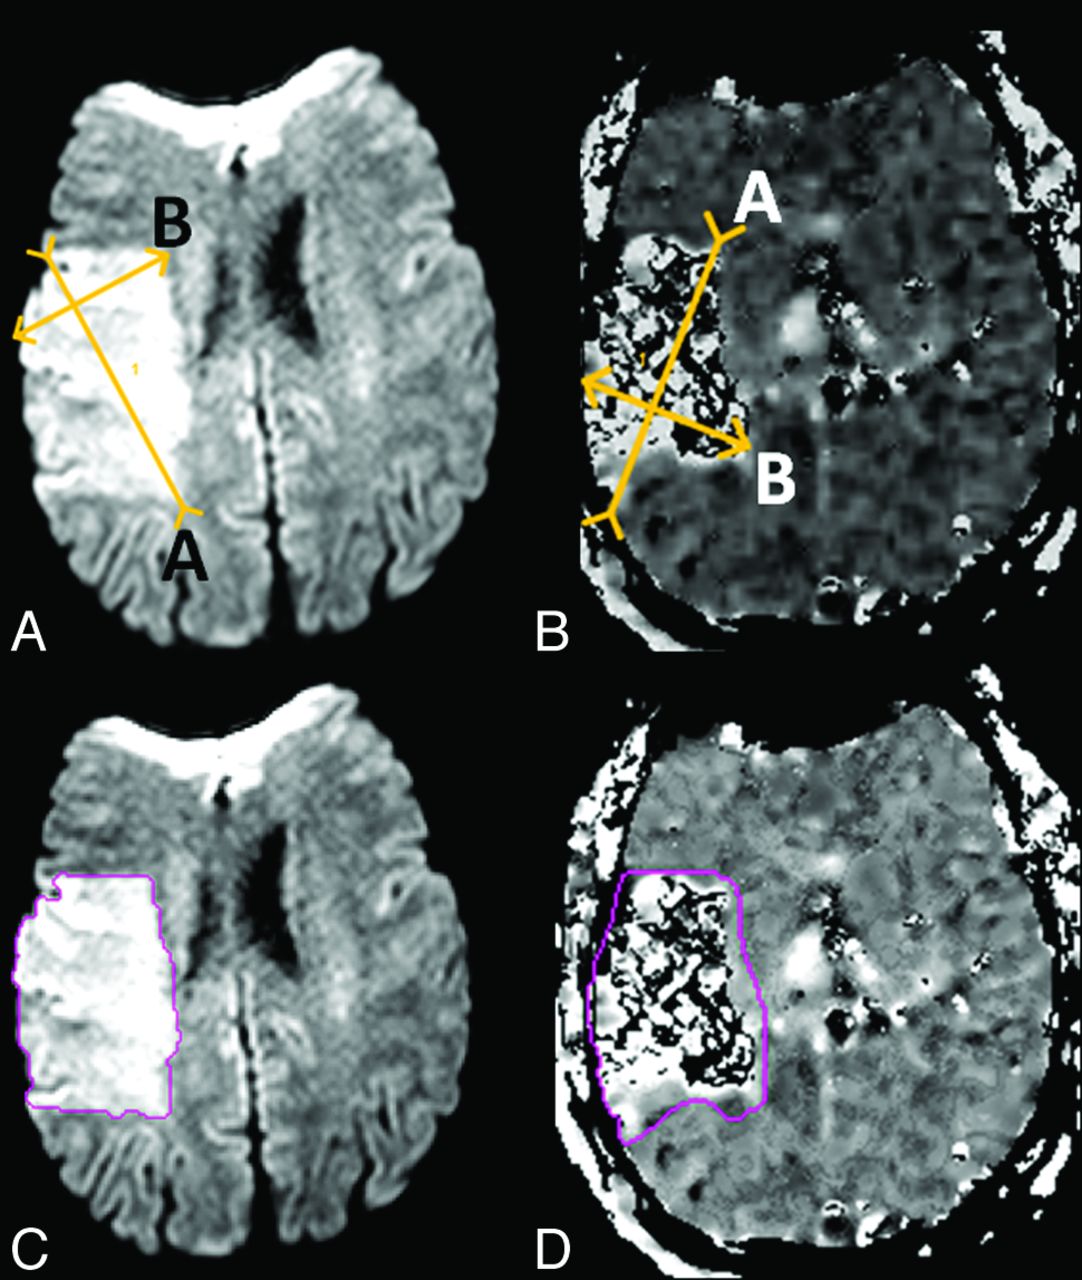

A rater (J.H.) measured the ABC/2 volume of DWI and MTT lesions by using a DICOM image viewer. After optimizing the window level settings, the 2 longest perpendicular linear diameters (A and B) on the section where the abnormality on DWI appeared largest were measured (Fig 1A). The same process was repeated on the section with the largest area of MTT abnormality (Fig 1B). With the use of these diameters, the product of the section thickness, and the total number of sections containing the lesion (C), the ABC/2 DWI and MTT volumes were calculated with the formula: volume = ABC/2. For discontinuous lesions, only the largest lesion area was measured. Multiple measurements were not performed across the discontinuous lesions. However, if the lesion was continuous and included multiple vascular territories, the measurement included the entire lesion area. For punctate lesions, the largest lesion area was measured.

Corresponding measurements for the ABC/2 method (A, DWI = 116.1 mL; B, MTT = 194.7 mL) and planimetric method (C, DWI = 116.2 mL; D, MTT = 248.4 mL) on paired sections placed independently by 2 different readers.

A rater (M.L.) with extensive experience and established rater reliability statistics measured the lesion volumes on the DWI and MTT maps by using a semi-automated quantitative, planimetric method in Cheshire (Boulder, Colorado).17 The intrarater and inter-rater reliability of the planimetric measurements of DWI and MTT was validated as a highly consistent and repeatable method by use of Cheshire in the Luby et al study.17 Lesion areas were segmented on a section-by-section basis, with user-selected seed points followed by user-driven editing (Fig 1C, -D).